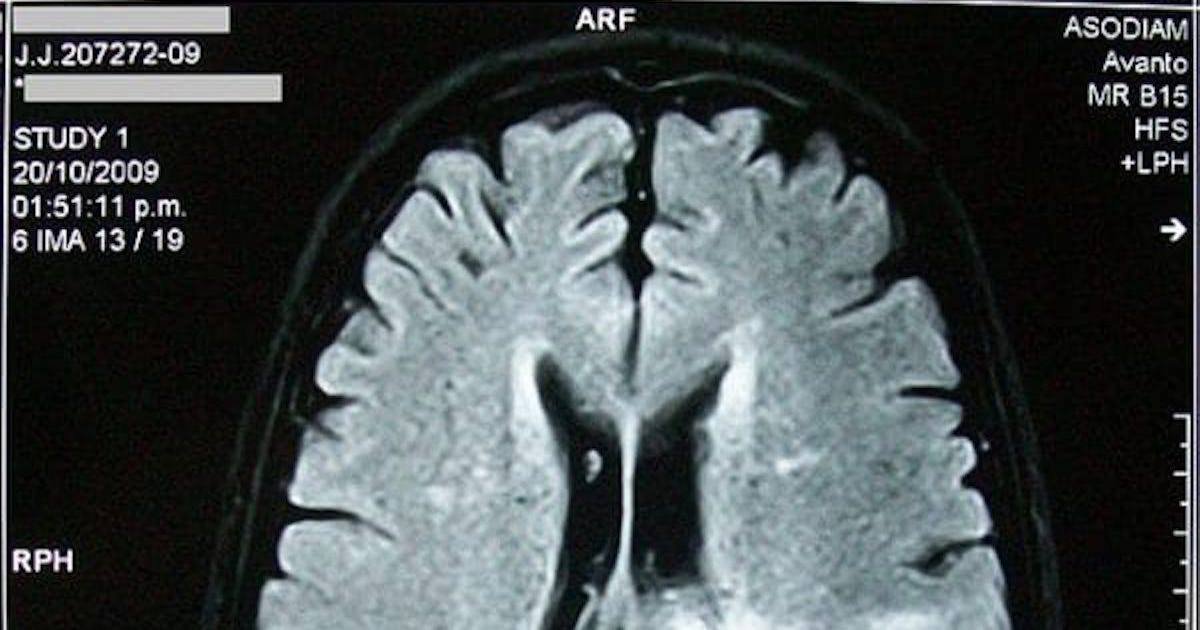

The doctor urged him to go to the hospital “immediately” for an MRI that revealed a mass in his brainstem, a moment that sent a wave of fear through both him and his mother, Sonora Swords.

With neurosurgical resources limited in Sioux City, Jones was transferred to Mercy Hospital, where another MRI was performed and surgery was initially discussed. However, uncertainty about the tumor’s location and its delicate position near the brainstem led doctors to refer him to a facility in Omaha for more advanced imaging.

“And then that’s when they told me that there was a 2-centimeter tumor inside of my brain stem,” said Jones. “It had fused to my brainstem walls.”

Despite the challenges, the biopsy confirmed that Jones had diffuse midline glioma (DMG), a rare and aggressive brain cancer known for its resistance to treatment, and that cannot be separated from the surrounding tissue.